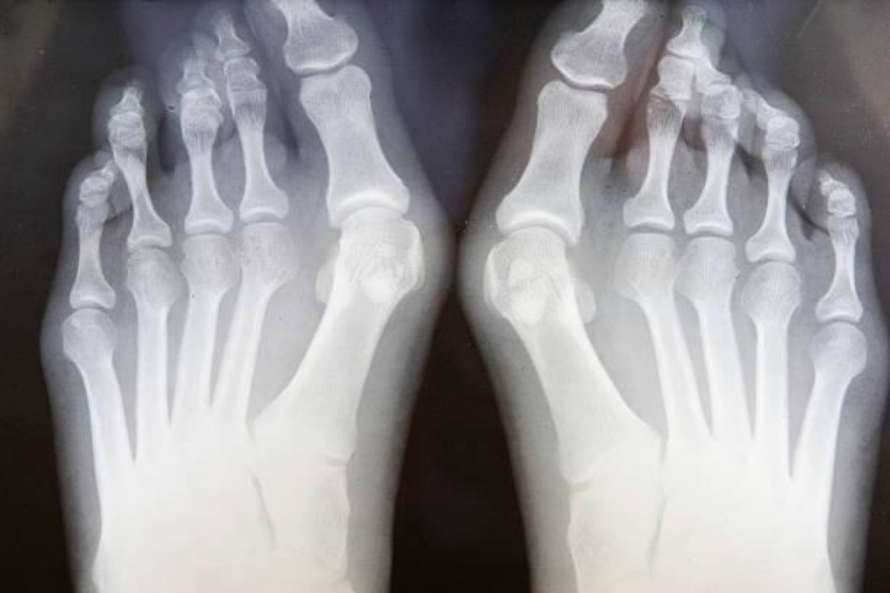

¿Cómo se diagnostica?

El diagnóstico se realiza con:

Inspección clínica: observación del pie al estar de pie y al caminar.

Radiografía de pie en carga: permite medir la desviación y clasificar si es leve, moderado o severo, lo cual orienta el tratamiento.